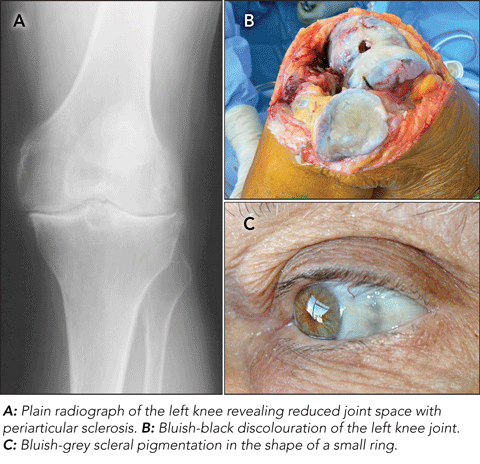

Black bones: a case of incidental discovery of ochronotic arthropathy